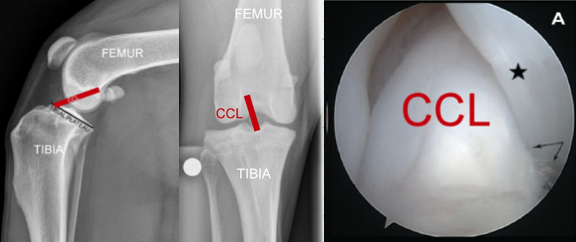

The femur does not normally slide off the back of the tibia because the canine ACL (CCL) holds it in place. The CCL is inside the knee and is a stout ligament that is oriented specifically to prevent the dog’s femur from sliding off the back of the tibia (or from the tibia from sliding forward out from under the femur). See next.

The cranial cruciate ligament is in the dog’s knee. The image on the left shows how the CCL is oriented in order to prevent the femur from sliding off the back of the tibia. The image in the middle shows where the CCL is located inside the canine knee as you look at the knee from the front view. The image on the R is an arthroscopic image looking inside a dog’s knee and showing an intact (i.e. normal) CCL. It is big, strong, smooth, white structure providing knee stability.